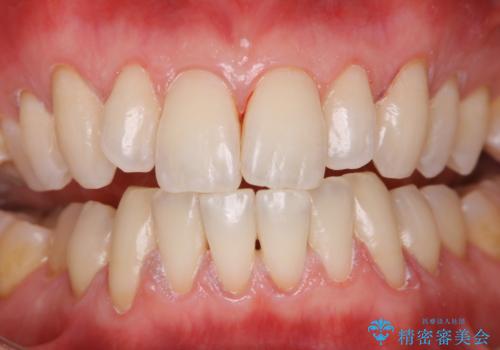

オールセラミッククラウン 銀歯を白く